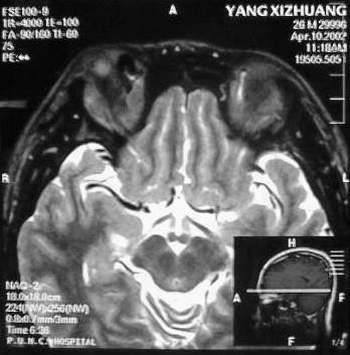

MRI及增强结果如下:

患者压颈及其它Valsava试验结果阴性。从MRI分析,在T1、T2、T+C检查该支血管均为明显流空现象,说明该血管血流速度很快,而从走行和分布看,眼上静脉可能性很大。也许也不能除外异常的眼动脉或异常血管。眶内主要可能的血管病变包括颈内动脉海绵窦瘘(高流窦)、AVM、眼眶静脉曲张、海绵状血管瘤、静脉性血管瘤、毛细血管瘤和眶内动脉瘤。。

1、颈内动脉海绵窦瘘:该患者临床有一部分支持该诊断。但从影像分析,海绵窦未见明显扩张;眼外肌未见明显充血扩张的长T1、长T2信号;颈内动脉海绵窦瘘常可见继发到血栓,可见到短T1、长T2的血栓信号。

3、AVM:患者目前的影像学资料尚不全面,但可符合该诊断。临床上改病常见于30岁左右年轻人,单侧发病,于本患较符合。问题在于临床没有明确的血管杂音,似乎难以解释。

纵上所述:本人觉得,患者AVM可能性较大,同时不能除外眶内动脉瘤。

根据MRI显示眼上静脉扩张可能性很大。眼上静脉扩张有几种原因:1.颈内动脉海绵窦瘘,2.眶尖肿瘤,3.甲亢,4.炎性假瘤.病人球结膜充血示静脉回流障碍,动脉瘤可能性小.根据病史,我认为排除1,2.则考虑3,4.查T3,T4.激素作诊断性治疗.